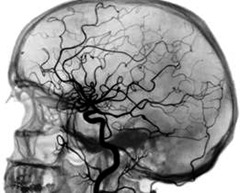

Исследование сосудов мозга называют церебральной ангиографией – после введения контраста за короткий промежуток времени делают несколько ангиограмм, отображающих венозную, артериальную, капиллярную фазы кровообращения. Ангиография мозга может быть прямой и непрямой. Выделяют каротидную и вертебральную прямую церебральную ангиографию. Чаще всего используют каротидный метод исследования – контраст вводят в шею, в сонную артерию. Вертебральная ангиография мозга отличается тем, что соединение йода вводится в позвоночную артерию. При непрямой церебральной ангиографии к сонной или позвоночной артерии подходят через другой крупный сосуд, например через артерию на бедре: вводят длинный катетер и нагнетают контраст.